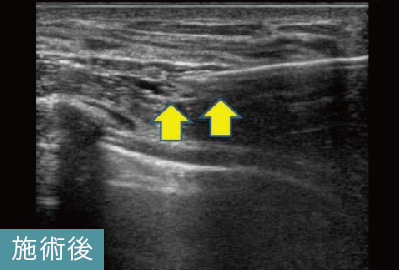

このケースは、他院でヒアルロン酸溶解注射による治療を受けても残ってしまったしこりの治療でした。しこりの取り残しは、治療前にしこりの正確な位置を把握していなかった可能性が考えられます。当院では、実際にしこりを確認しながらヒアルロン酸内に的確に注射を行います。このケースでも完全になくなっていることが確認できます。